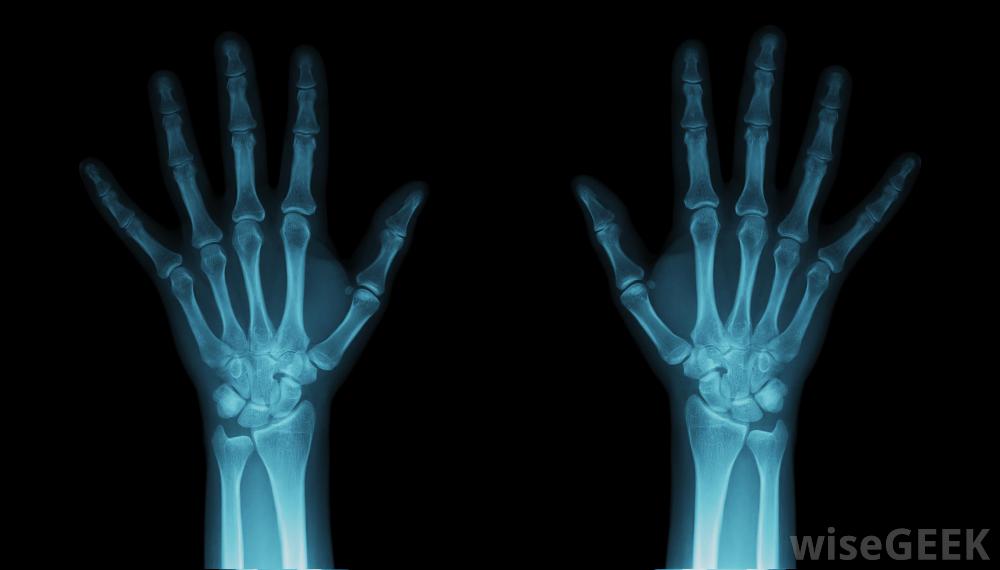

手腕韌帶撕裂首先要經過醫生的檢查。為了了解損傷的程度,將對手腕進行x光或磁共振成像(MRI)掃描。如果不能得到清晰的圖像、關節鏡或微型攝像機,可能會被插入腕關節。醫生還會詢問您以前的健康史以及您在同一關節上的任何損傷。

可能需要對手腕進行X光檢查韌帶損傷。